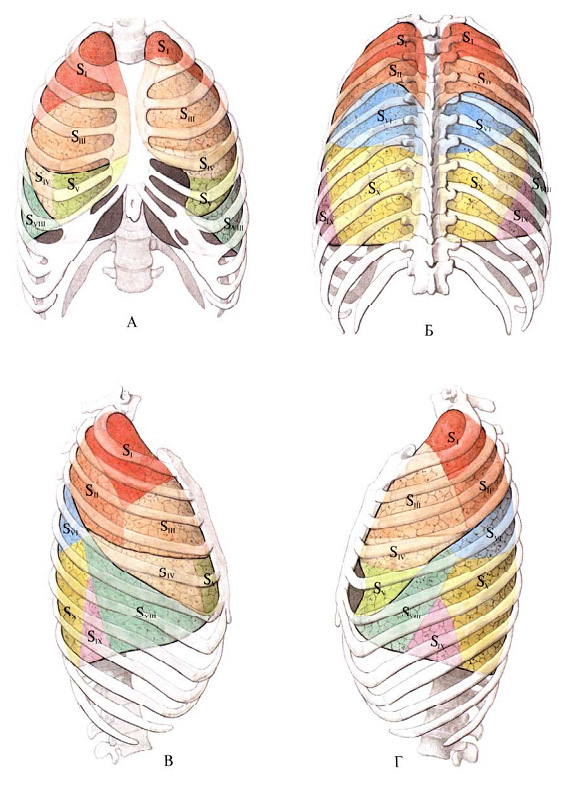

Анатомические изображения сегментов легких различных животных

Раздел: Другие животные